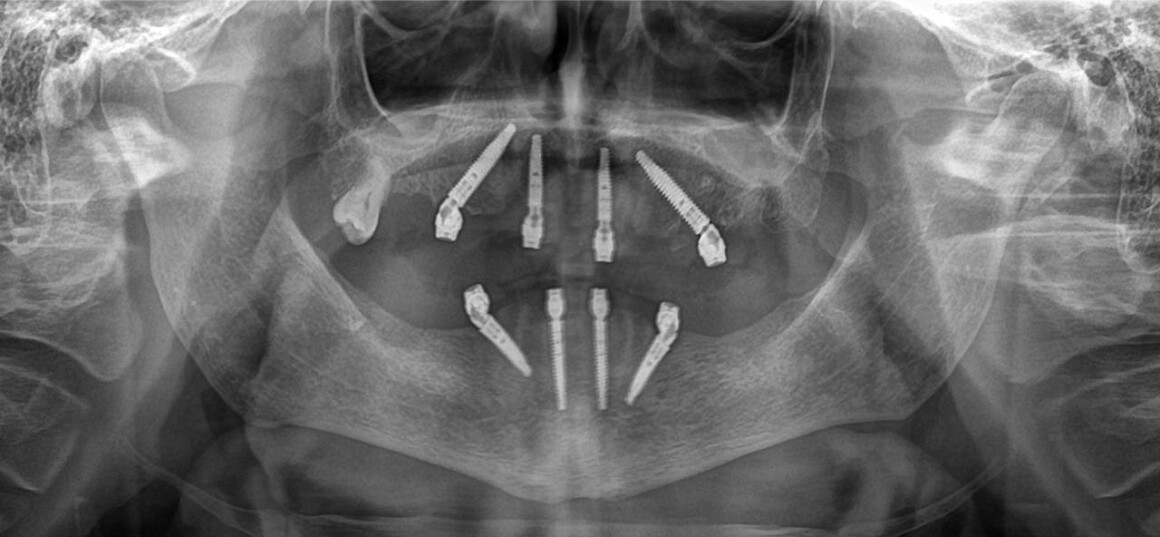

Имплантация ALL on 4 на верхней и нижней челюстях в день операции

Имплантация ALL on 4 на верхней челюсти